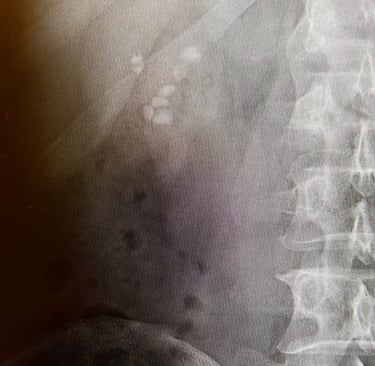

Sağ böbrekte 8 adet taş